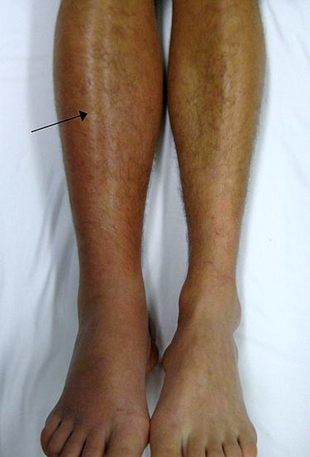

Par kādu patoloģiju lb. kājas apakšstilbā varētu domāt? Kādi izmeklējumi būtu nepieciešami diagnozes apstiprināšanai? (vairākas atbildes)

100%